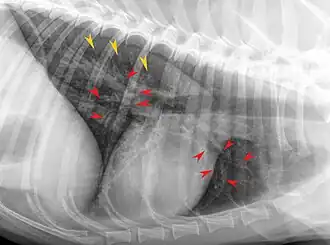

Neben dem klinischen Bild umschließen die diagnostische Maßnahmen Röntgenaufnahmen der Lunge beziehungsweise eine Computertomographie zur Abklärung des Ausmaßes der Veränderungen. Wesentlich jedoch ist eine Bronchoskopie mit dem Nachweis eosinophiler Granulozyten in der hierbei gewonnenen BALF. Hierbei müssen weitere Auslöser eosinophiler Entzündungen der unteren Atemwege wie Lungenwurmbefall, hier insbesondere Angiostrongylus vasorum, allergische Prozesse und Herzwurmerkrankung ausgeschlossen werden. Die Bronchoskopie selbst zeigt eine hyperämisierte und manchmal verdickte Mukosa und muköses bis mukopurulentes, grüngelbliches Sekret in den unteren Atemwegen.